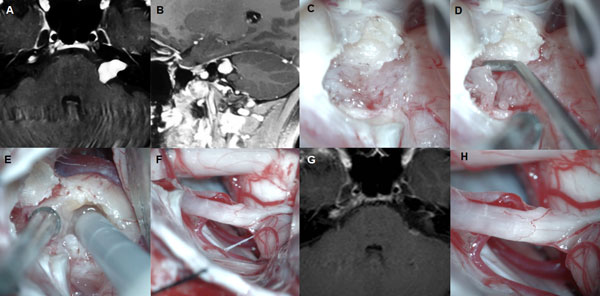

Figura 3: Paciente femenino de 40 años, operada de SV T3b izquierdo. A-B: RM preoperatoria. C-F: hallazgos intraoperatorios. G: RM postoperatoria, H: imagen intraoperatoria del lecho tumoral y descompresión del complejo VII-VIII

Figura 4: Paciente femenino 20 años, operado de SV T4b derecho. A-C: RM cerebral preoperatoria, D-I: imágenes intraoperatorias, D-F descompresión intratumoral con aspirador ultrasónico, G-H descompresión del complejo VII-VIII, I: oclusión del CAI con cola de fibrina. J-L: RM cerebral postoperatoria